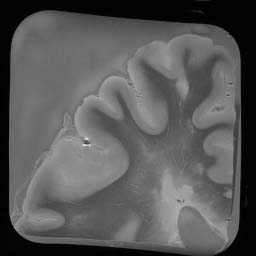

7T_brain

256 × 256